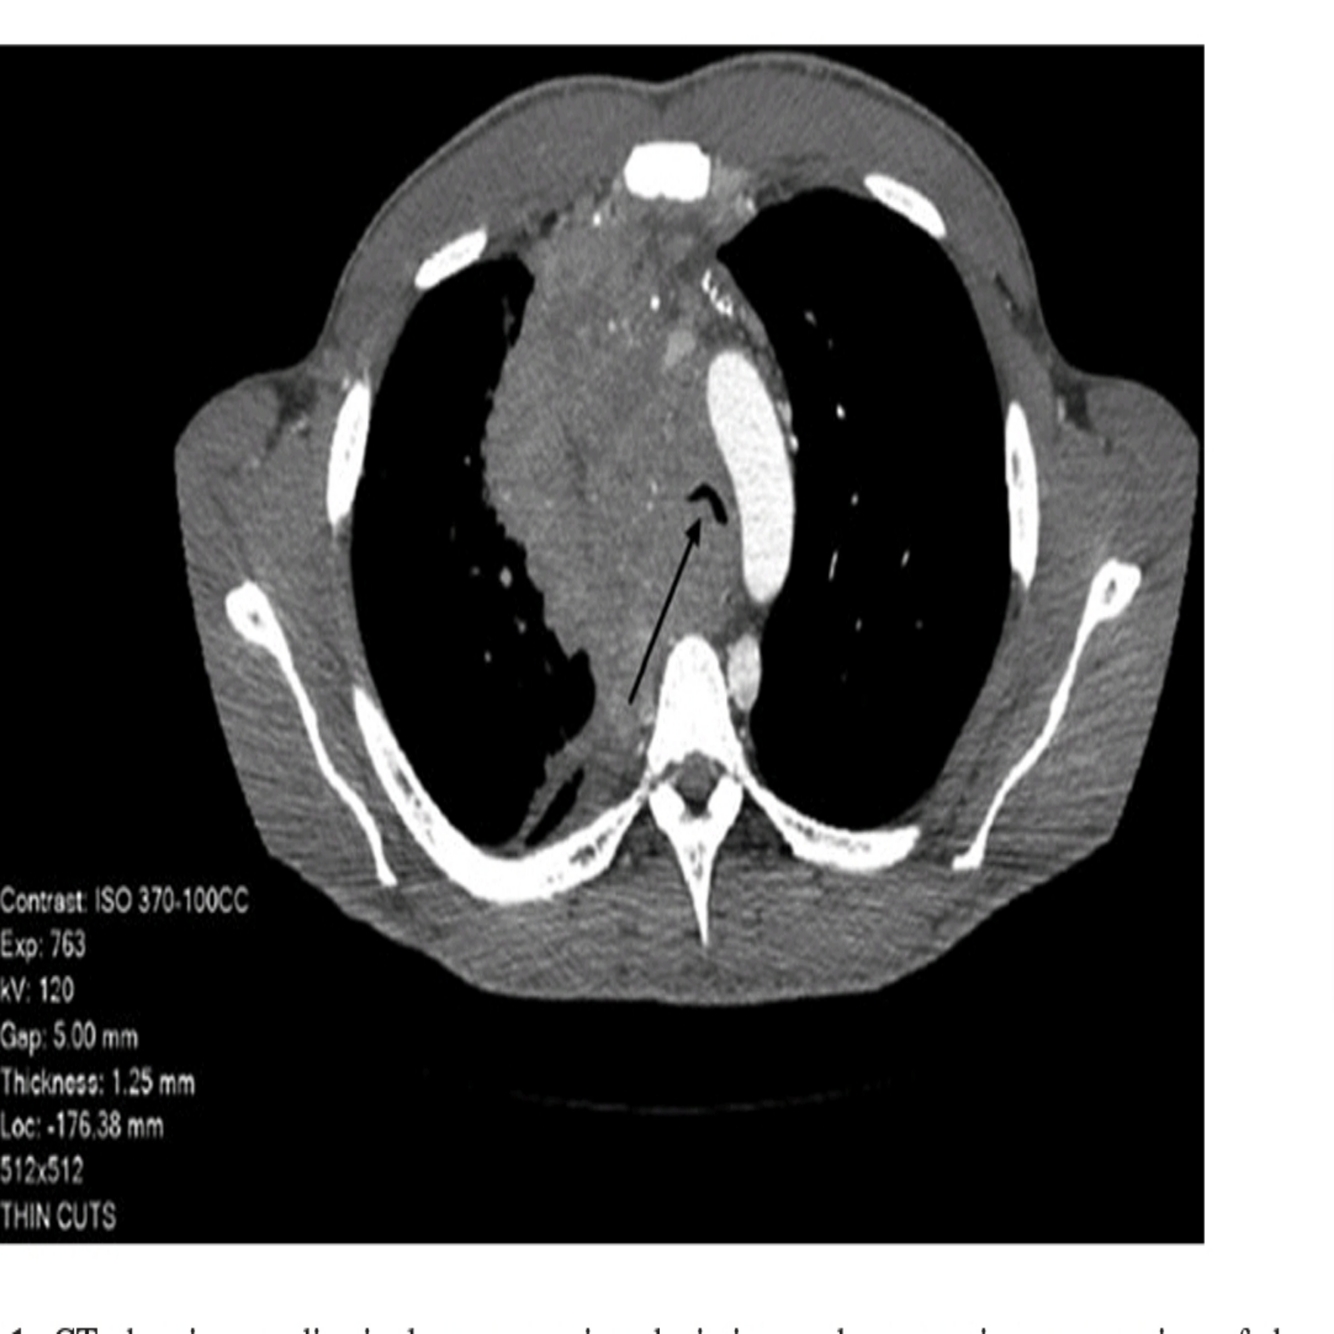

What do the images above show and what is the differential diagnosis based on the appearance seen in the images above?

○ The chest X-ray (Fig. 47.1) shows diffuse bilateral coalescent opacities, whereas the CT chest (Fig. 47.2) shows ground-glass opacification, reflecting an overall reduction in the air content of the affected lung. It is also possible to visualize bronchial dilatation within areas of ground-glass opacification.

Differential diagnosis include

(a) ARDS,

(b) congestive heart failure,

(c) pulmonary hemorrhage,

(d) pneumonia,(

e) transfusion-related acute lung injury, and

(f) non-cardiogenic pulmonary edema.